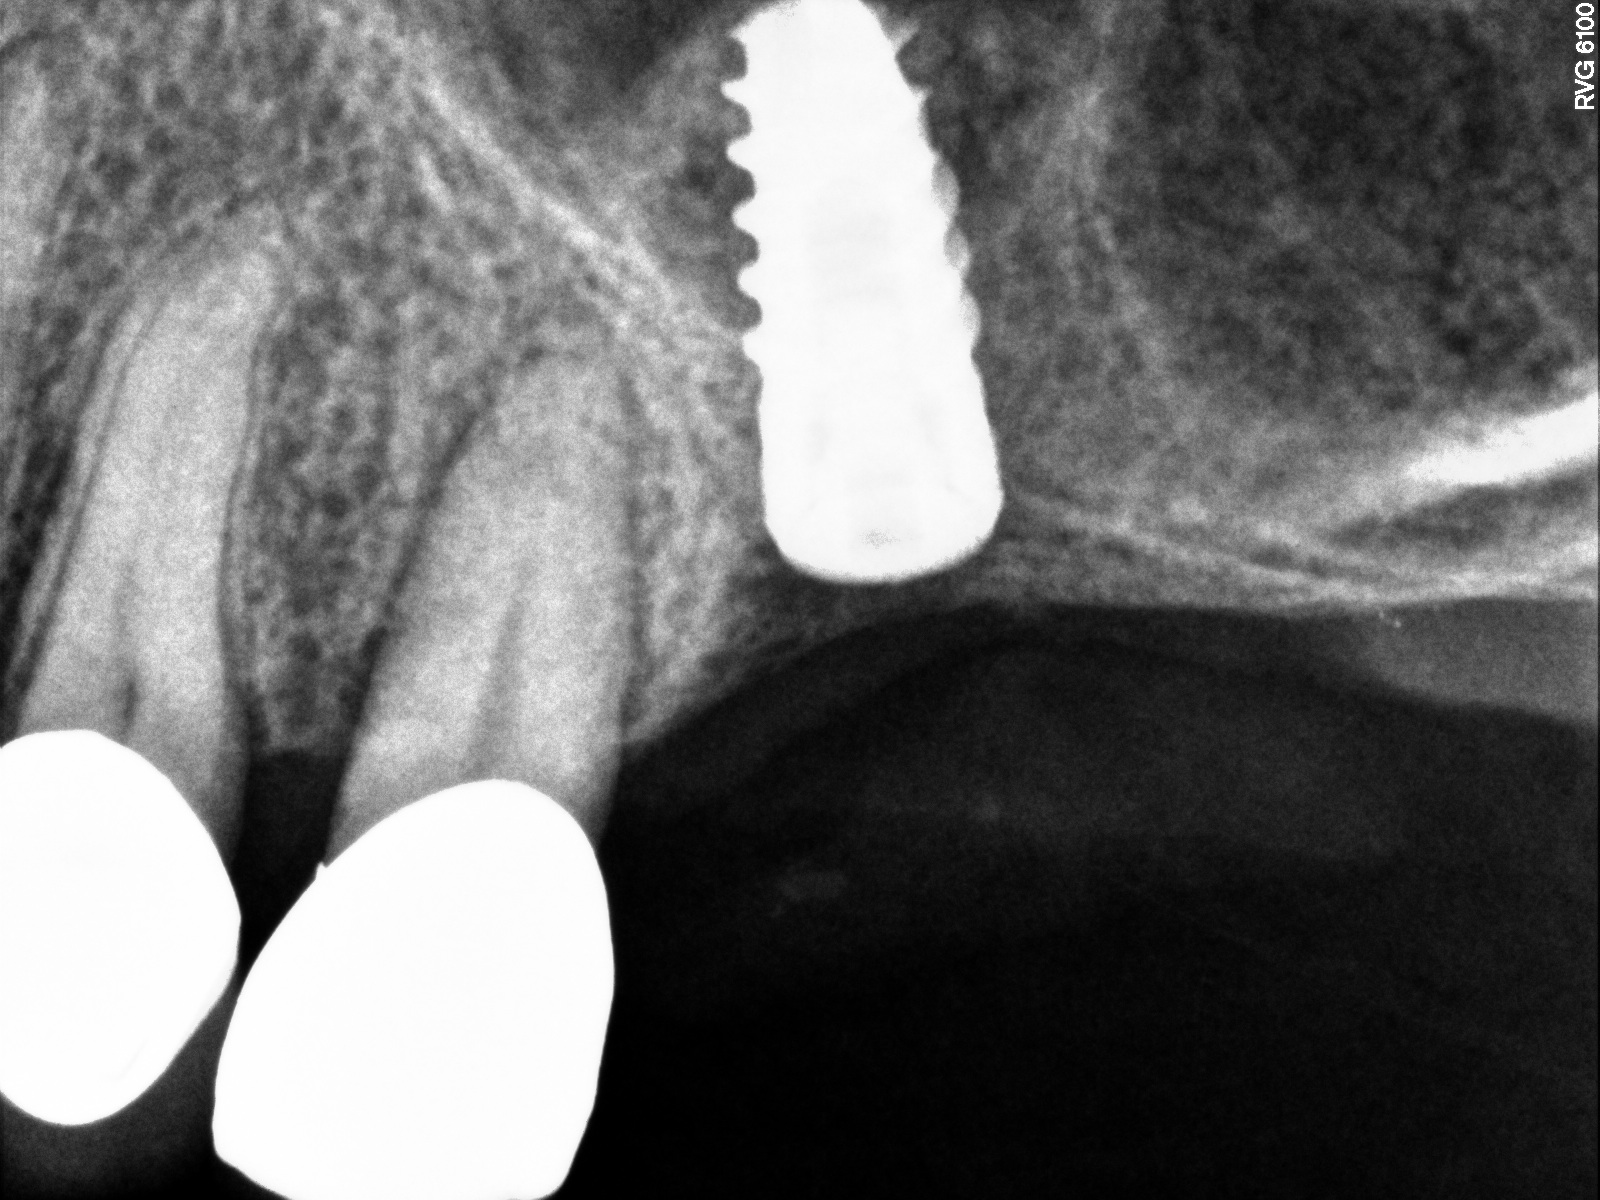

Radiograph of implant N o. 3 and sinus augmentation, day of placement. There is about 2 mm to 3 mm of native bone, and the sinus has been raised about 8 mm to 9 mm.

Fig. 10

A 7-month postoperative radiograph of the restored implant No. 3.

Fig. 11

The implant is then delivered and should be well stabilized in the bone. If there is any mobility of the implant, it can either be placed a little deeper (if there is enough native bone) or the implant can be removed and the procedure aborted, in which case it would be a two-stage procedure. This should rarely occur with the tapered designed implant, even with only 2 mm of native bone. Using a bone-level platform-shifting implant (or a tissue-level designed implant) is critical, as the hard and soft tissue will establish a biologic width. If an external hex type of implant is used and the shoulder is placed at the bone level, an expected bone loss of 1.5 mm to 2 mm will occur.24 Figure 10 shows proper bone-level implant depth placement with a platform-shifting design. In this case, a 3-mm healing abutment was placed at the time of surgery to avoid a secondary uncovering surgery, but an implant-level healing abutment could have been placed instead. As can be seen, there was only about 2 mm to 3 mm of native bone height. The membrane was raised about 8 mm to 9 mm. Comparing the radiograph on the day of surgery (Figure 10) to the 6-month postoperative radiograph (Figure 11) shows no loss of native bone, as well as the positive change in appearance of the grafted bone. The 3.5-month CBCT scan (Figure 12) shows good healing of the bone with no coronal bone loss. With minimal native bone present, as in this case, the use of a non-platform-shifting or non-tissue-level implant design could be problematic. After 1.5 mm to 2 mm of crestal bone loss, an external hex designed implant could develop instability with possible implant failure. If a non-tapered implant is used and bone loss occurs during healing, migration of the implant into the sinus could potentially occur. The surgeon can use either a healing abutment or implant-level closure screw over the implant shoulder. With patients who tend to use their tongues to explore or play with the area, or if the area is under a removable partial denture, a closure screw is recommended.